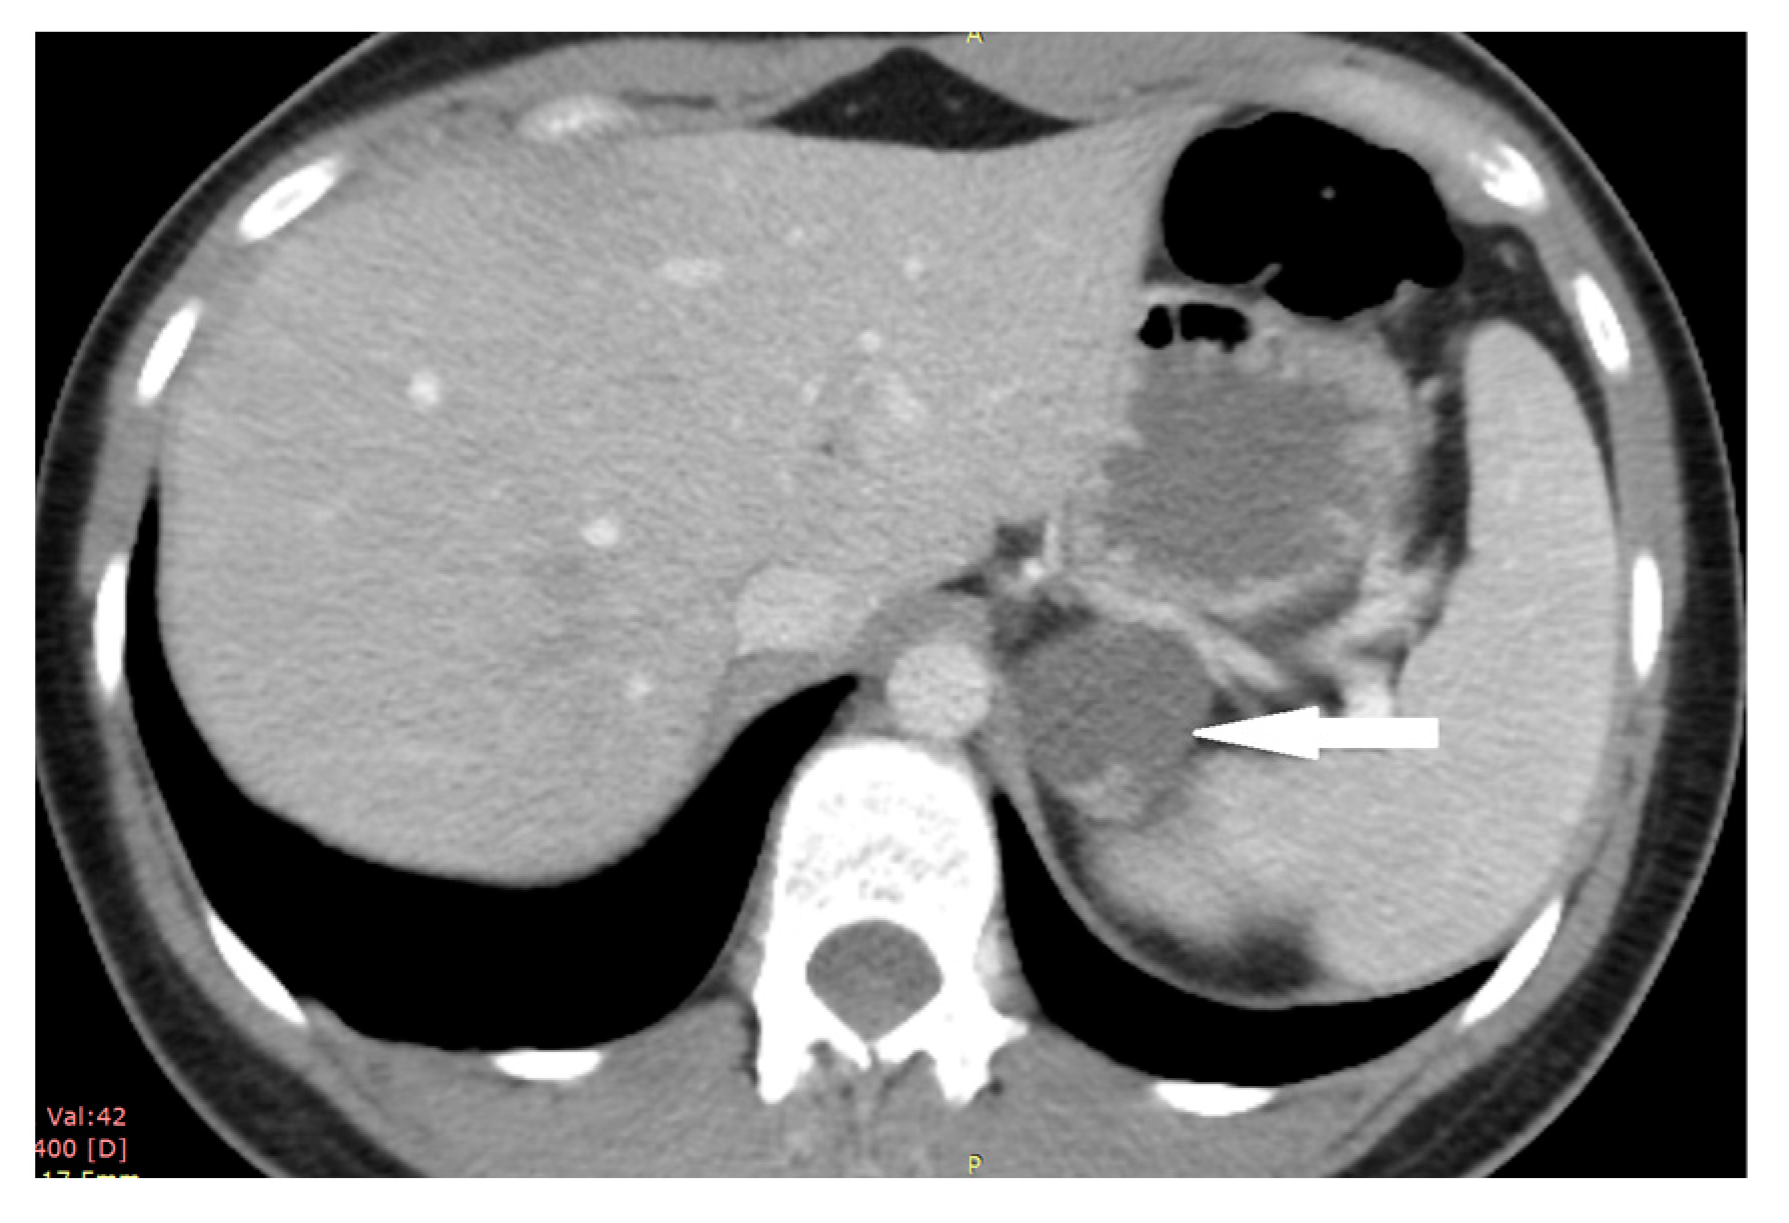

2.4. Case 4